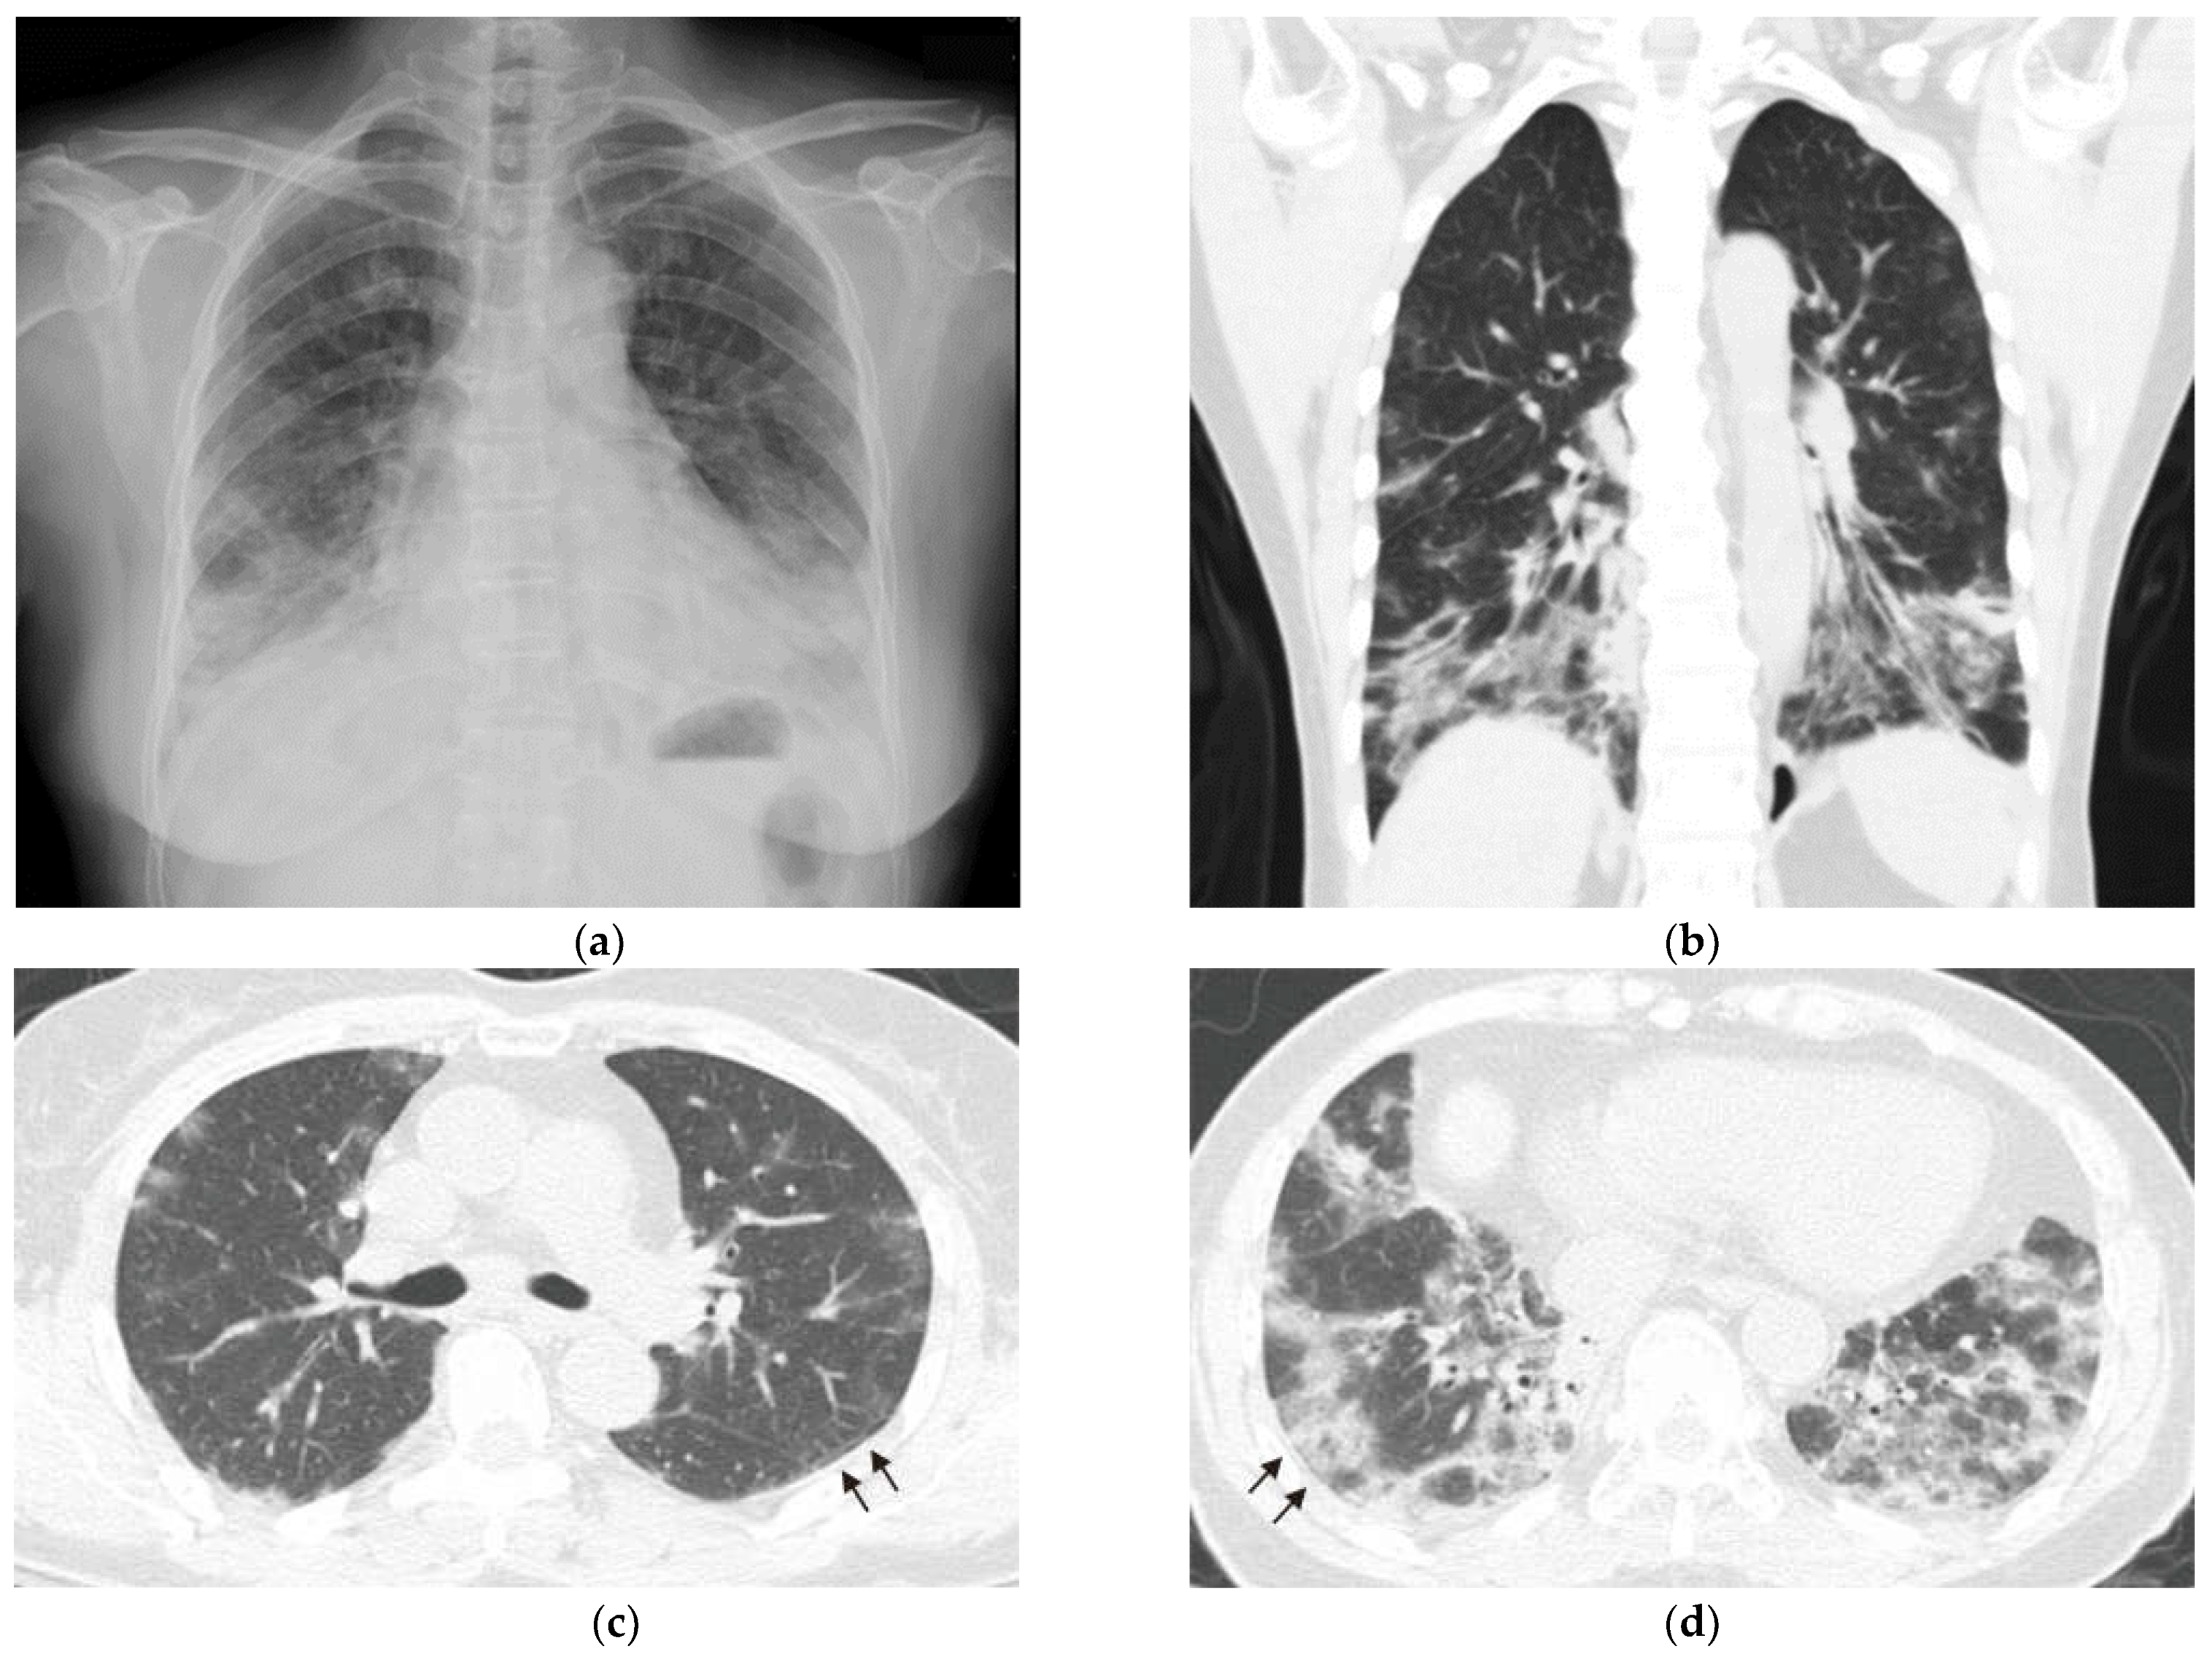

2. Case Report